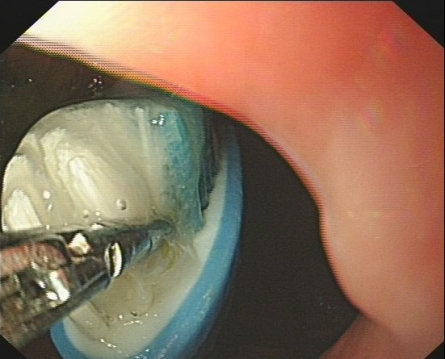

進(jìn)鏡后發(fā)現(xiàn):胃腔內(nèi)可見大量食物殘?jiān)?可見一把長(zhǎng)約10余厘米牙刷沉陷其中,底端牙刷柄銳利。郭朝書考慮到牙刷長(zhǎng)度大,質(zhì)地硬,底端銳利,使用常規(guī)取異物器械不易抓取,加之胃內(nèi)容物多,影響操作視野,且患者體質(zhì)特殊,若操作時(shí)間過長(zhǎng),食物殘?jiān)菀渍`吸;且從胃里取出來要經(jīng)過細(xì)長(zhǎng)的食管,特別是食道的三處狹窄,取出難度可想而知,若貿(mào)然暴力將其拖動(dòng),可能對(duì)胃、食管、咽喉黏膜造成二次損傷。在充分評(píng)估后,制定了聯(lián)合使用鱷魚鉗和異物網(wǎng)籃取異物的方案,在佘智華、陳瓊芳護(hù)士嫻熟地配合協(xié)作下,快速、安全、順利地將牙刷取出。